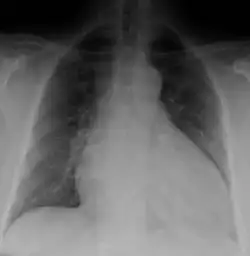

Dilated cardiomyopathy on CXR

Generalized enlargement of the heart is seen upon normal chest X-ray. Pleural effusion may also be noticed, which is due to pulmonary venous hypertension.[28]

The electrocardiogram often shows sinus tachycardia or atrial fibrillation, ventricular arrhythmias, left atrial enlargement, and sometimes intraventricular conduction defects and low voltage. When left bundle-branch block (LBBB) is accompanied by right axis deviation (RAD), the rare combination is considered to be highly suggestive of dilated or congestive cardiomyopathy.[29][30] Echocardiogram shows left ventricular dilatation with normal or thinned walls and reduced ejection fraction. Cardiac catheterization and coronary angiography are often performed to exclude ischemic heart disease.[28]